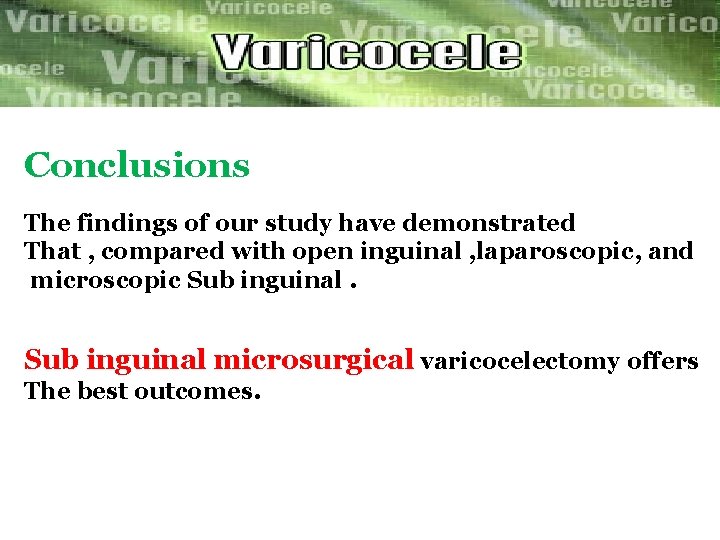

Objective: to compare the outcomes of the different surgical Techniques used in varicocelectomy wich include: Inguinal approach (40 p ) Laparoscopic approach (40 p) Subinguinal microscopic approach (40 p) The assessment included postoperative complications , and Postoperative semen analysis and pregnancy rate after 18 mon. The result was…………. .

Postoperative complications 20% 18% 16% 14% 12% 10% hydrocele 8% recurrence 6% 4% 2% 0% inguinal laparoscopic microscopic subinguinal Inguinal: hydrocele 13% +13% recurrence. Laparoscopic: 20% +18%. Microscopic subinguinal : 0% +0. 5%.

Laparoscopic 18% Inguinal 13% Microscopic subinguinal 0. 5% Recurrence

Improvement of sperm motility and concentration 78% 76% 74% 72% 70% sperm mobility and concentration 68% 66% 64% 62% 60% inguinal laparoscopic microscopic subinguinal Inguinal: 65% Laparoscopic: . 67% Microscopic subinguinal : 76%

Pregnancy rate after 1 year 40% 35% 30% 25% 20% pregnancy rate 15% 10% 5% 0% inguinal laparoscopic Inguinal: 28% Laparoscopic: . 30% Microscopic subinguinal : 40% microscopic sub inguinal

Conclusions The findings of our study have demonstrated That , compared with open inguinal , laparoscopic, and microscopic Sub inguinal microsurgical varicocelectomy offers The best outcomes.